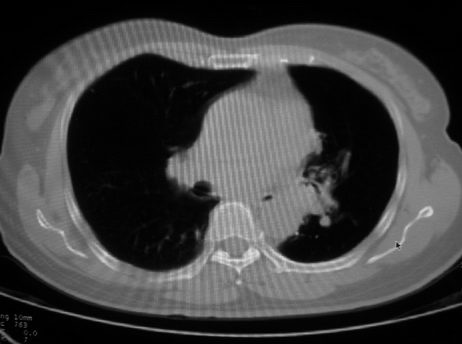

以下是引用李衡钧在2008-7-24 14:24:00的发言:[br]左侧胸廓变小,左肺上叶见大面积致密阴影,其内有空洞及不规则钙化。上纵隔略向左移位,上肺胸膜增厚。左肺门及纵隔淋巴结增大。右肺见散在的致密结节影。[br]印象:继发性肺结核。